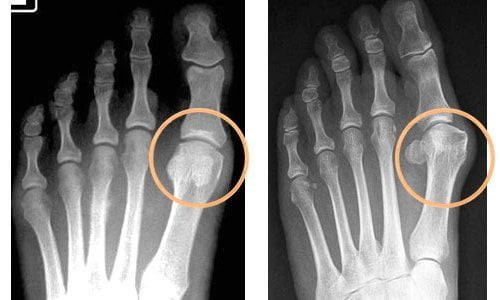

Основным методом диагностики артроза стопы является рентгенография. С ее помощью диагностируют сужение суставных щелей, костные деформации, снижение плотности костной ткани и другие характерные признаки остеоартроза. Если рентгенологическое исследование малоинформативно, больному делают МРТ.

Рентгенологические стадии артроза:

- На рентгенограммах нет никаких изменений. Заподозрить болезнь можно лишь по легким болям при ощупывании или сгибании пальцев.

- При рентгенографии у больного выявляют сужение суставной щели, которое косвенно указывает на повреждение хрящей.

- На снимках отчетливо видны признаки поражения костной ткани. У многих пациентов появляются выраженные деформации пальцев стопы.